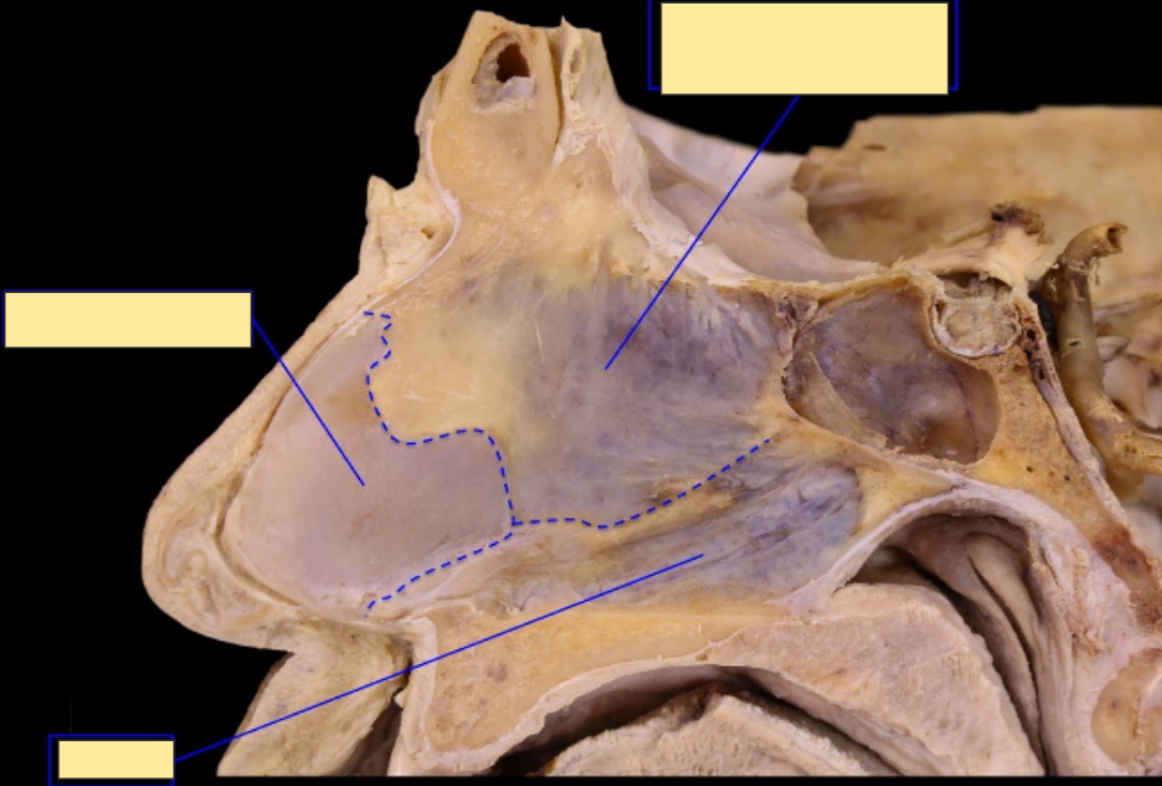

label this saggital section of the medial wall of nasal cavity

A